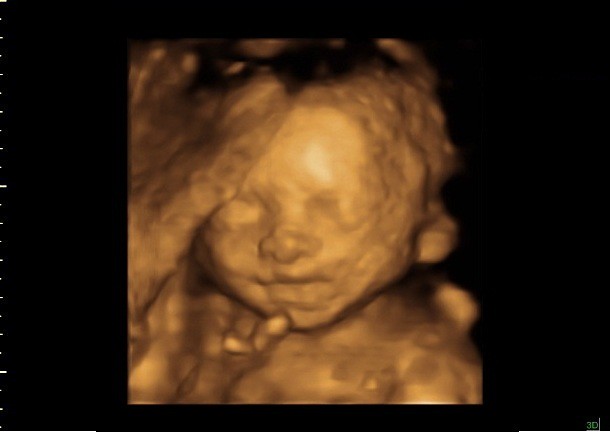

3D Ultrasound 24 Weeks Pregnant

3D Ultrasound 24 Weeks Pregnant. I just scheduled a 3d/4d ultrasound for february 7th. 3d ultrasound pic at 24 weeks.

At this stage, the baby has put on some weight and filled out to make features more visible, yet still enough fluid in front of baby’s face to obtain great images. 38 weeks. I had mine the day i turned 25 weeks, and i thought they came out wonderful! Healthcare providers don't usually rely on 3d ultrasound, but it can help diagnose certain conditions before birth.

Medical Professionals May Prefer Conducting Them Between Approximately 24 And 34 Weeks.